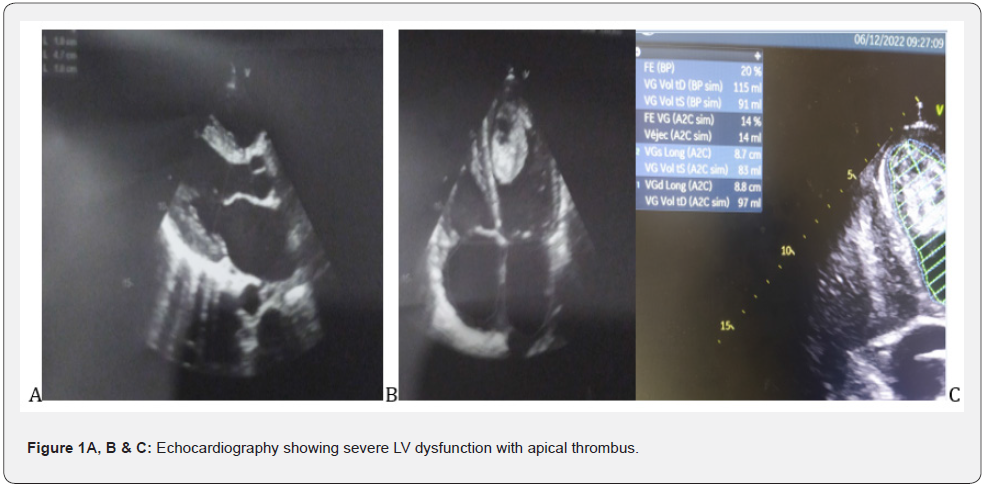

Echocardiography showed a non-dilated, slightly hypertrophied LV with severe dysfunction and 20% EF, with a huge mobile thrombus measuring 42 x 23 mm in the LV, no significant mitro-aortic valve disease.The MRI scan showed a late subpericardial enhancement in severe bi ventricular dysfunction with a huge mobile intra LV thrombus suggesting acute myocarditis. The patient was put on strict rest and an IV diuretic treatment with monitoring of the diuresis, an effective anti-coagulation, a bolus of solumedrole 120 mg over 3 days and per-os relay of 60 mg with progressive degression. The evolution was marked by a clear regression of the congestive signs, an improvement of the general state of the patient over 7 days and a recovery of the EF to 40% vs 20 at admission. A disruption of the thrombus after 7 days of anti-coagulation with a minimal migration giving a light splenic and hepatic infarction without significant clinical repercussions. The patient was discharged after 12 days in hospital on Coversyl 5 mg/d; Cardensiel 2.5 mg/d; Sintrom 7.5 mg/d and Solupred 60 mg/d with a 3 month tapering programme.

Myocarditis is an inflammatory disease of the myocardium defined by the Dallas histological criteria. Diagnosis requires the demonstration of a predominantly lymphocytic myocardial inflammatory infiltrate defined by the presence of >14 leukocytes/mm3 including more than 4 monocytes > mm3 and 7 CD3+ T lymphocytes/mm3, associated with myocyte necrosis of non-ischaemic origin [4]. The pathophysiological hypotheses are variable and include both cell lysis related to direct viral toxicity, and inflammatory phenomena related to the activation of the innate immune response (production of pro-inflammatory cytokines) and then specific cellular response [5- 6]. In certain situations, this activation may be excessive and lead to significant destruction of the cardiomyocytes, causing left ventricular dysfunction as seen in our patient, which can evolve into a state of cardiogenic shock if not managed immediately, which worsens mortality in the most severe forms (fulminant myocarditis). In all cases, this cardiomyocyte necrosis is responsible for the elevation of troponin, as confirmed in our patient with troponin levels of 300 mg, which is a key element in the diagnostic suspicion without any electrical sign of myocardial suffering of ischaemic origin [7]. The clinical phenotype of myocarditis is very polymorphic, which makes its positive diagnosis difficult; the diagnosis is suspected in the presence of clinical symptoms associated with an elevation of the tropo-nine and possibly inflammatory markers. The picture of acute heart failure corresponds to the appearance of signs of heart failure over a period of less than two weeks. This picture of fulminant myocarditis is often preceded a few days before by an influenza-like episode, which is consistent with our presentation where we find a history of influenza-like illness favoured by an unfavourable socio-economic level in our third world countries. The left ventricular dysfunction can be severe and responsible for shock because of diogenesis. Echocardiography usually shows a non-dilated, hypertrophied left ventricle (in relation to myocardial oedema) in our patient we find a slight hypertrophy at 10 mm of the wall and 10 mm of the IVS (Figure 1 A & B) with altered systolic function [8] as well as severe LV dysfunction in our patient with an EF of 20% (Figure 1C). Myocardial magnetic resonance imaging (MRI) has become an indispensable non-invasive examination in the management and follow-up of myocarditis (Figure 1D & E). The diagnosis of myocarditis is based on the presence of two of the following three Lake Louise criteria [9] : Myocardial hyperhaemia, demonstrated by early global gadolinium enhancement of the myocardium in a T1-weighted sequence; regional or global myocardial oedema, demonstrated by hyper signal in a T2- weighted sequence; myocardial necrosis or fibrosis, most often multifocal, in the pericardium, as seen in the images of our patients (Figure 3 F and G), demonstrated by late gadolinium enhancement in a T1-weighted sequence. The presence of a pericardial effusion is an additional argument for the diagnosis of myocarditis which further supports the diagnosis in our patient with the pericardial effusion slide found on MRI. For the treatment in the general case, the recommendations of the ESC are to propose in first intention a symptomatic treatment of the cardiac insufficiency by the diuretic for the decongestion; the IEC and beta blockers for their effects anti-remodelling. Studies concerning the curative treatment of myocarditis mainly concern chronic forms, which are known to have an unfavourable evolution in the medium and long term, with progressive degradation of cardiac function. The diagnosis is then made during biopsies carried out in the context of recently discovered dilated cardiomyopathy. Various immunosuppressive treatments (prednisolone, cyclosporine, cyclophosphamide) have been tried in myocarditis. In a recent prospective randomised double-blind study comparing placebo versus prednisone and azathioprine in 85 patients with non-viral chronic lymphocytic myocarditis who had symptoms of heart failure for more than six months despite conventional medical treatment (TIMIC Study), In the TIMIC Study, an improvement in left ventricular ejection fraction (LVEF) and a reduction in left ventricular enddiastolic volume were found in 88% of the 43 patients treated, whereas cardiac function deteriorated in 83% of the 42 patients who received placebo [10-12]. In the light of these studies, we recommended that patients be treated with bolus corticosteroids (solumedrole 120) as an adjuvant to the corticosteroids, and we noted a favourable evolution under treatment with a good clinical and echocardiographic improvement (Figure 3 F and G).